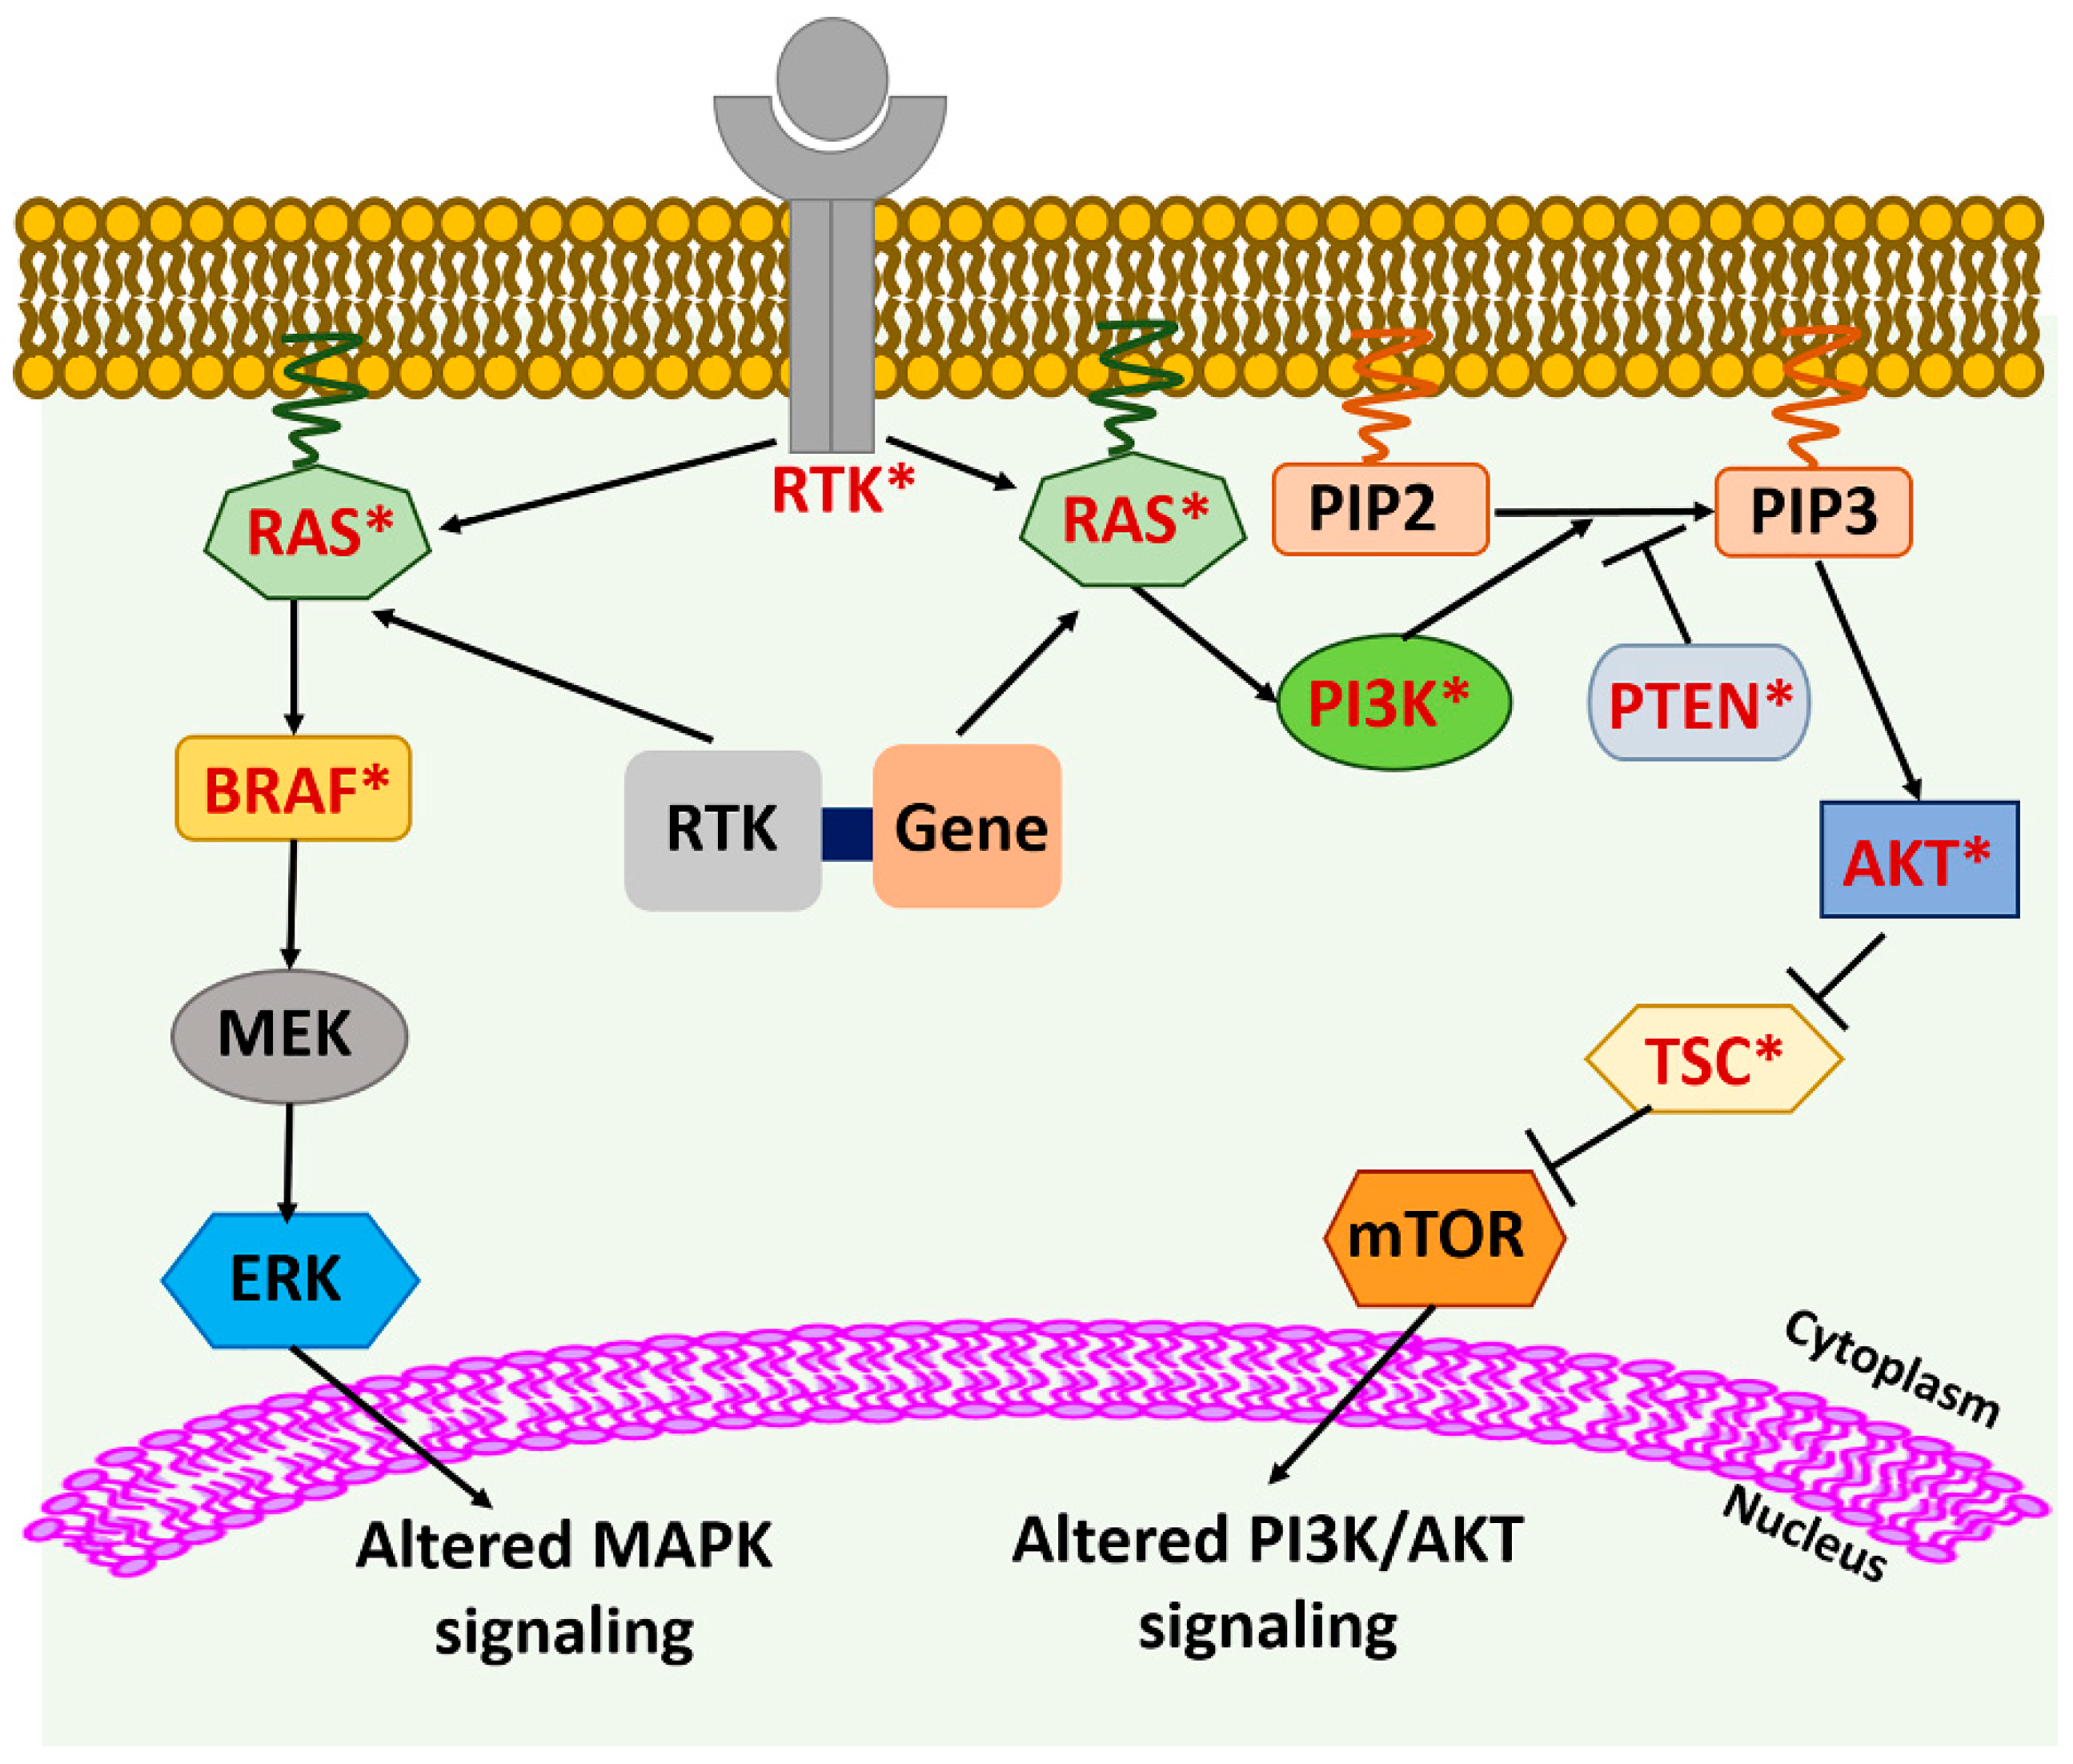

Thyroid Cancer Explore vol.3 no.2(2201 「Thyroid Cancer Expl。Thyroid Cancer | SpringerLink。Advances in Functional Imaging of Differentiated Thyroid Cancer。